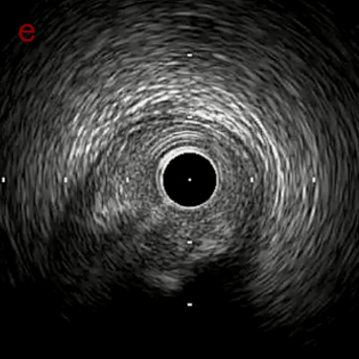

IVUS after OAS high speed 3回追加

IVUS imaging after high speed 3回追加

a,b,cの十分な石灰化のsanding。

High riskのbias所見へと変わっていったdの部位に関してはpinpoint OASを行うことでinjuryなく治療できた。

Cutting + DCBの方針に。